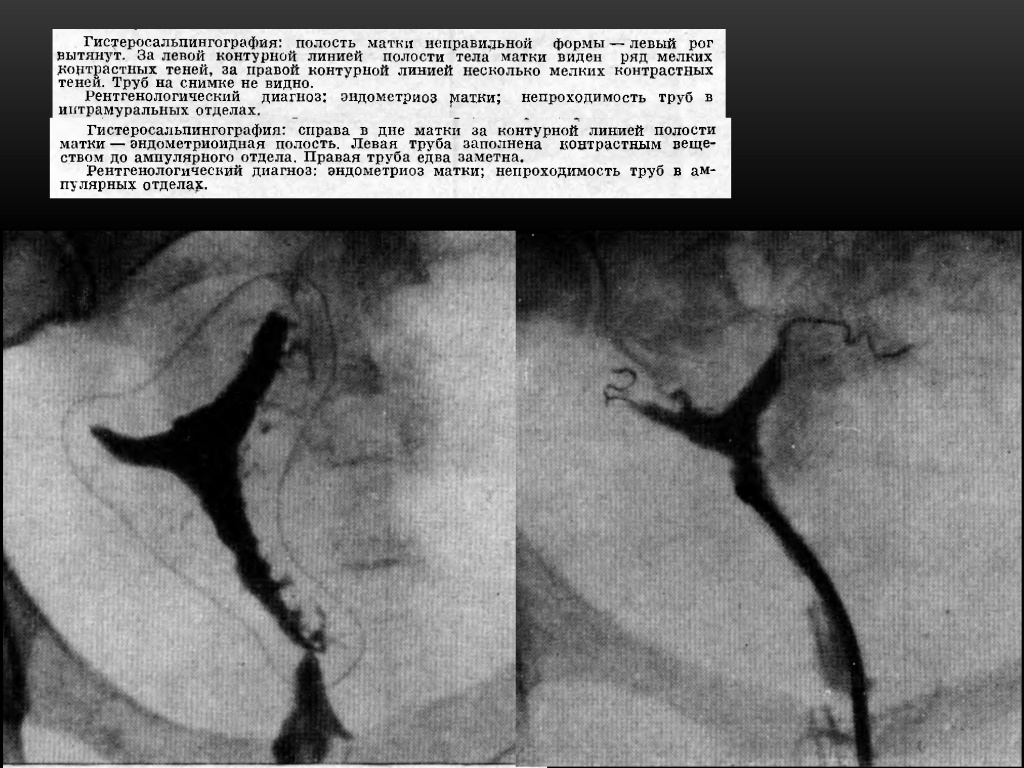

Медицинские снимки: Проходимость маточных труб